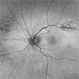

- 57 year-old male referred for decreased vision from optometrist. His only complaint was floaters and the letters were moving on the screen. He had never been out of the country, but is a farmer. Upon examination, our retina specialist found a bot fly larvae with numerous tracks made in this patient's retina. Patient was treated with laser to kill the larvae which was successful and he has been monitored yearly.